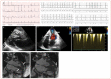

Rhythm and conduction disturbances and sudden cardiac death are important manifestations of cardiac involvement in autoimmune rheumatic diseases (ARD), which have a serious impact on morbidity and mortality. While the underlying arrhythmogenic mechanisms are multifactorial, myocardial fibrosis plays a pivotal role. It accounts for a substantial portion of cardiac mortality and may manifest as atrial and ventricular arrhythmias, conduction system abnormalities, biventricular cardiac failure or sudden death. In patients with ARD, myocardial fibrosis is considered to be the hallmark of cardiac involvement as a result of inflammatory process or to coronary artery occlusive disease. Myocardial fibrosis constitutes the pathological substrates for reentrant circuits. The presence of supraventricular extra systoles, tachyarrhythmias, ventricular activity and conduction disturbances are not uncommon in patients with ARDs, more often in systemic lupus erythematosus, systemic sclerosis, rheumatoid arthritis, inflammatory muscle disorders and anti-neutrophil cytoplasm antibody-associated vasculitis. In this review, the type, the relative prevalence and the underlying mechanisms of rhythm and conduction disturbances in the emerging field of cardiorheumatology are provided.